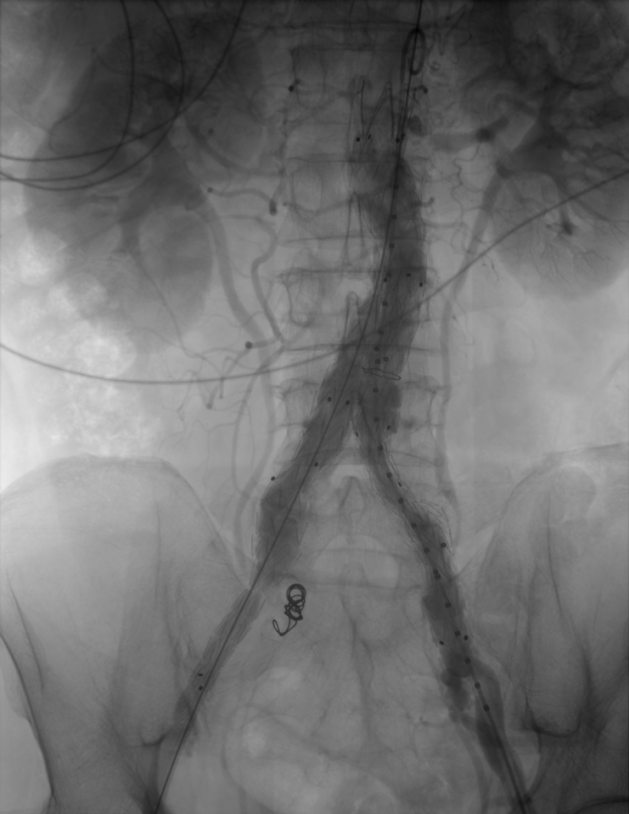

患者于2024年11月2日在外院查CT发现腹主动脉下段及双侧髂总动脉动脉瘤。次日,随即至我院微创介入科住院,并完善相关检查。

▶ 血管三维成像明显发现左肾动脉以下至双侧髂总动脉多处呈瘤样扩张